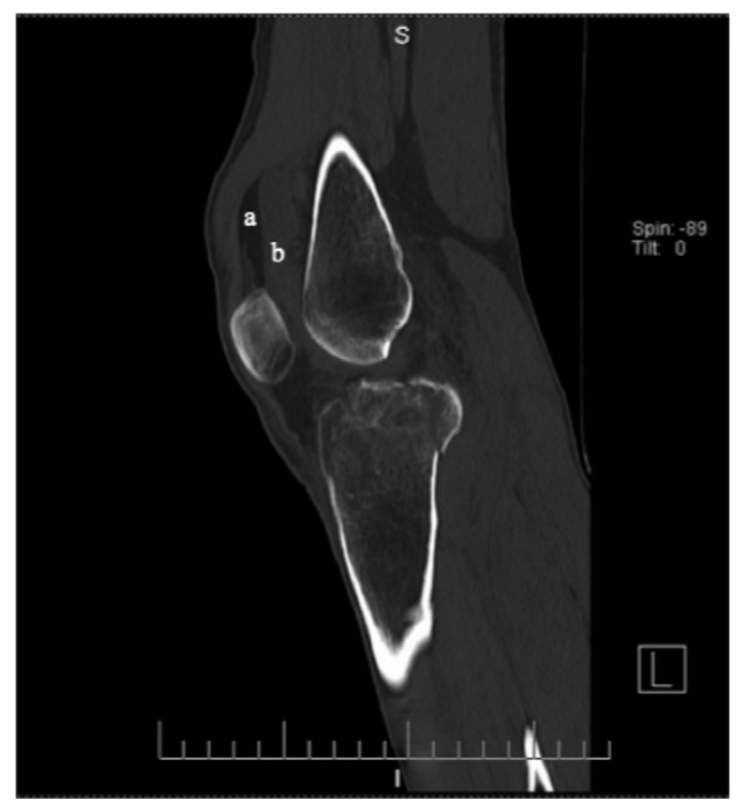

病例4股骨颈骨折,在CT横断面骨窗上未见明显液体分层(a),在软组织窗(b)可见高密度血肿影(箭头所示,CT值为50HU)。